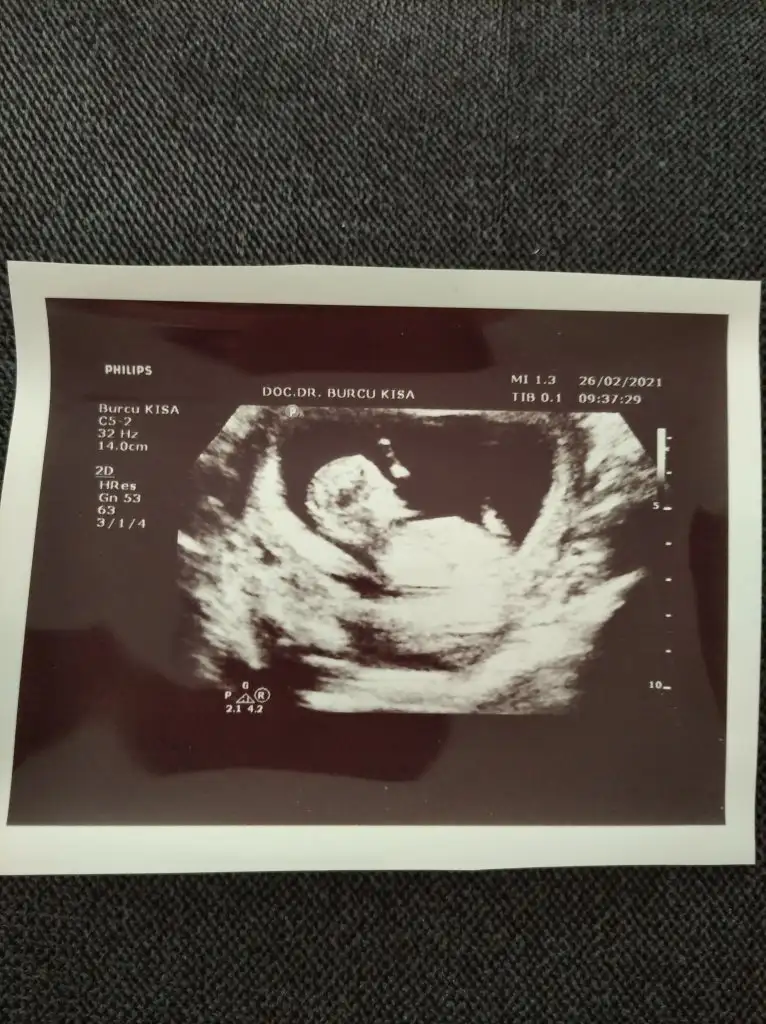

Bende çıktım kızlar muayeneden. İkili de yaptık. 0,44 çıktı ense kalınlığı. Burun kemiği de görüldü. Cinsiyet tahmini de yaptı ama kesin değil 1 ay sonra kesin söylerim dedi. Nub u falan da net gördüm ama çıktı aldığı fotoğrafta yok sanki